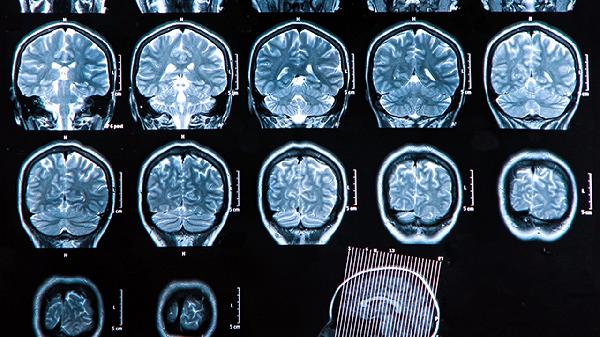

大脑出现阴影需要尽快前往医院进行详细检查,常见影像学手段包括CT或核磁共振,可以帮助明确病因。这种情况往往提示大脑某部位可能存在异常,但具体原因需要结合检查结果判断。

影像资料中的“阴影”是医学影像报告中形容异常影像的术语,通常并非特指某种疾病,而是表明有疑似病灶出现。大脑的阴影可能由多种原因引起,比如脑梗死、脑肿瘤、出血、脑囊肿或炎症感染等。不管是良性病变还是需要进一步治疗的疾病,科学诊断是解开疑问的关键。